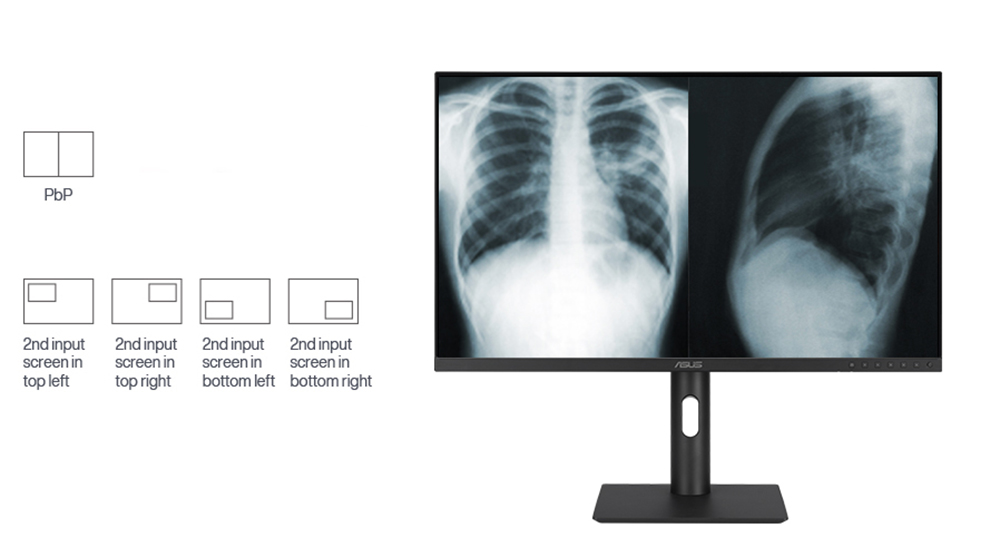

farklı izleme seçenekleri

yan yana resim (pbp)

farklı kaynaklardan gelen görüntüler ekranda yan yana koyularak aynı anda iki farklı ayar görüntülenebilir, her pencerenin renk ayarı srgb, dıcom, kullanıcı modu 1 veya kullanıcı modu 2 şeklinde yapılandırılabilir.

resim içinde resim (pip)

ikinci kaynaktan gelen görüntüyü, pencere halinde ekranın bir köşesine kolayca konumlandırabilirsiniz.